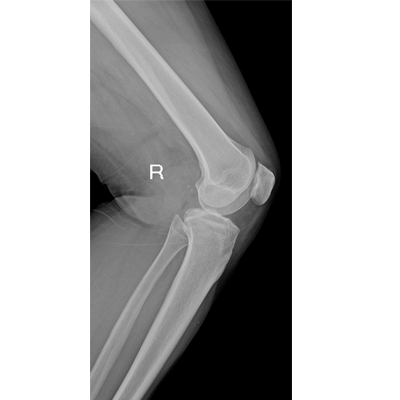

用于影像科、急診室、病房、ICU、手術(shù)室等多場(chǎng)景應(yīng)用。

● 數(shù)字化無線平板成像,操作簡(jiǎn)便,成像質(zhì)量高